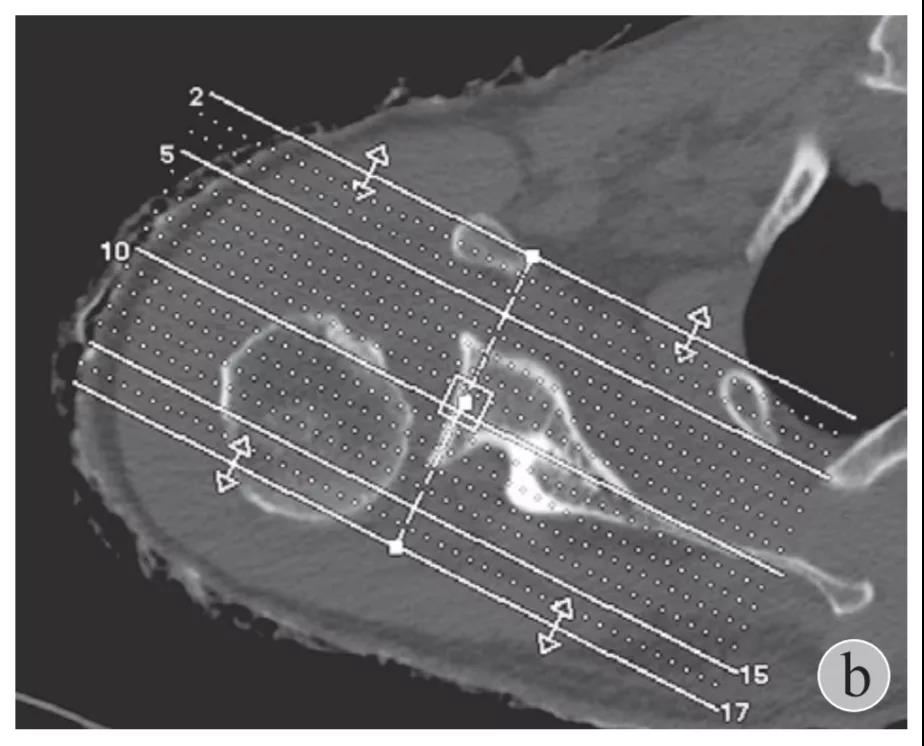

就诊我院后完善CT,诊断明确——左肩关节后脱位: